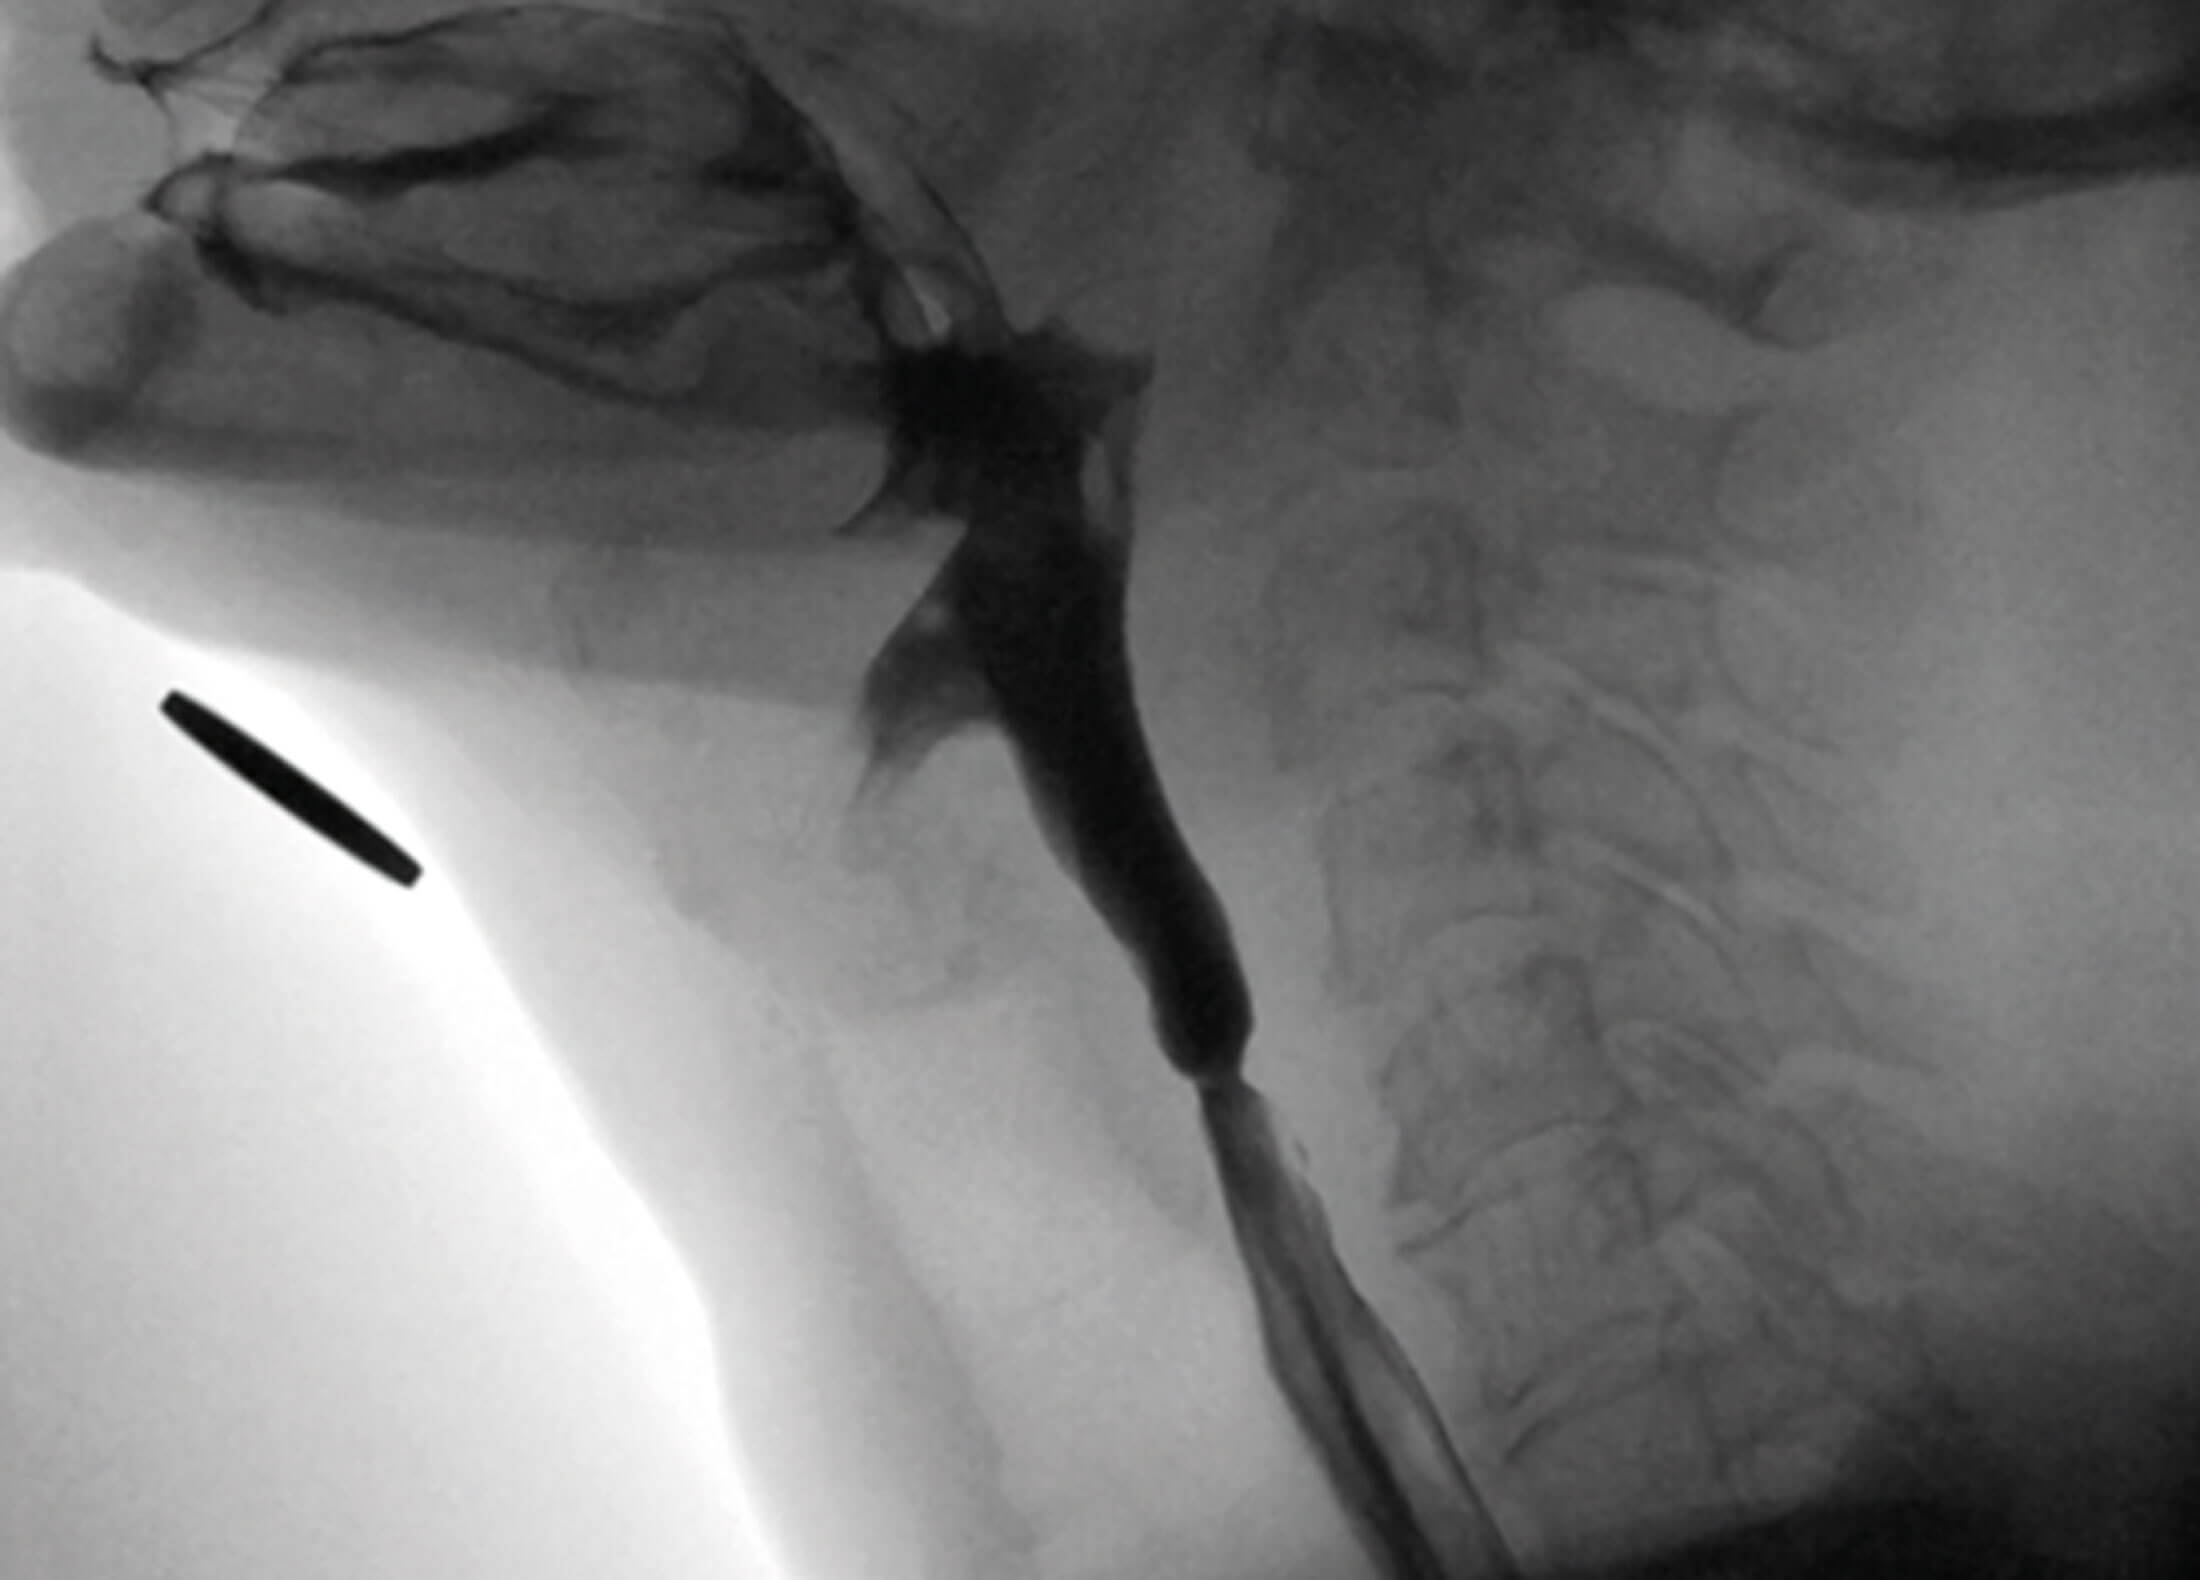

Muscle tension dysphagia: an underdiagnosed problem

In this article, the authors introduce the description of swallowing problems which have been recently attributed to muscle tension dysphagia (MTDg). The authors are clear that this is a diagnosis of exclusion, and it is important to rule out other...